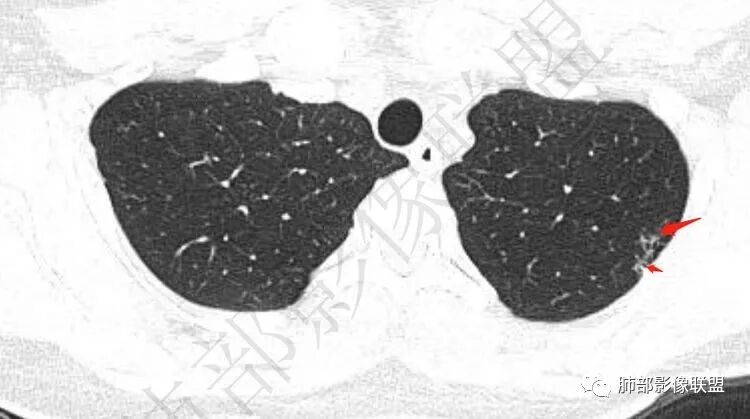

两肺多发囊或空洞(部分腔内不干净可见间隔影)+多发结节 (右侧胸膜下的结节显著)+左肺尖斑片影。年轻女性,体检发现。考虑结核?鉴别PLCH(奇异囊加结节,吸烟男性多见),转移瘤(要有原发肿瘤病史)

【每日晨读】双肺上叶多发薄壁空洞

2.双肺多发薄壁空洞影、条索影及结节影,边界较清楚,密度偏高不柔和,散乱,但有成簇倾向或堆积感,胸膜下分布为主,双肺上叶分布为主。

3.空洞相当不规则,缺乏张力,未见血管穿行,未见壁结节,未见液平。

4.双肺门及纵隔未见肿大淋巴结。未见胸腔积液。